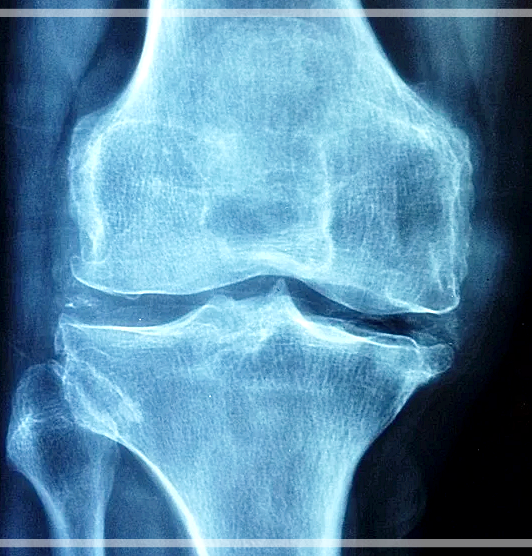

1. 관절 건강

관절염이 있는 연골을 정상 연골과 비교해보았더니 황 농도가 1/3 정도가 낮은 것이 확인이 되었다고 합니다. 그래서 msm을 섭취해주면 관절 건강에 도움이 될 수 있는 것인데요, 실제로 45~90세의 관절염 환자들을 대상으로 MSM을 섭취하게 하였더니 관절 통증과 뻣뻣함 등의 관절 기능의 불편함이 감소되었다는 실험 결과가 나타났어요.